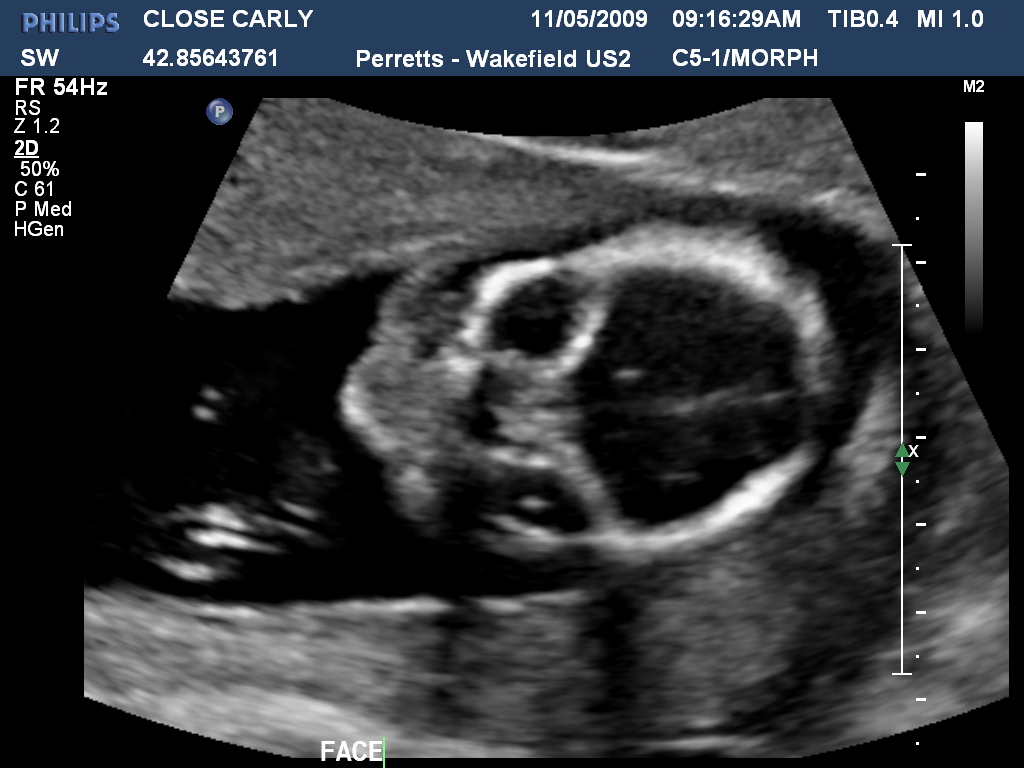

Wow how time flies! Carly is now 159weeks pregnant and now definately showing. Last week we had the first real scan and got to see hands and feet, the bub was quite active and gave the radiologist a hard time! Below are a few photos of both the bub and the expectant Mum to be!